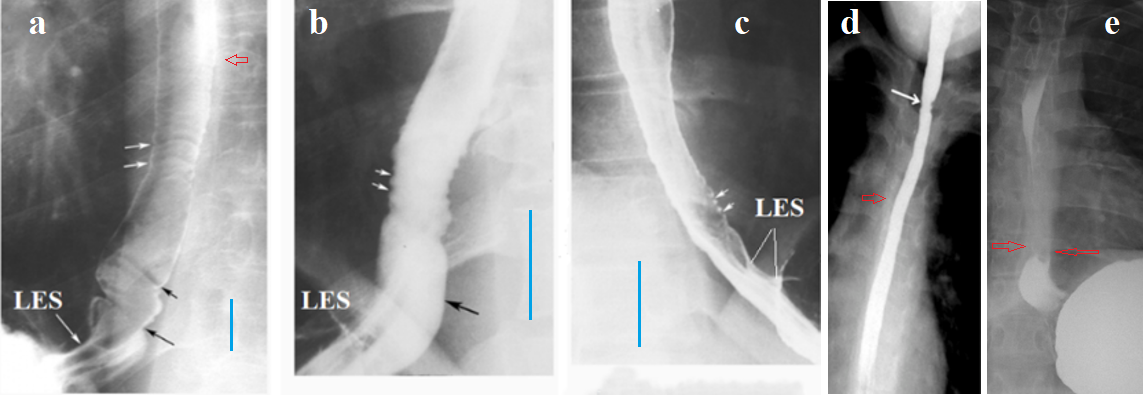

X-ray image of the esophagus and LES in EoE

All authors pay attention to the narrow lumen of the esophagus but do not compare it to any normal values. The presence of erosions and ring-like indentations is considered characteristic of EoE. Since patients with GERD always shortens the LES, I searched the literature for radiographic studies of patients with EoE where the EGJ was captured. In each of the 10 such cases, LES damage was found, characteristic of GERD (Figure 4).

Figure 4. Radiographs of the esophagus and LES in patients with EoE. (a, b, c) from the article by Zimmerman et al. [26]. (a) In addition to ring-like indentations, the authors describe a smooth tapered structure located between the esophagus and the stomach. This is a short LES with several longitudinal folds (my designation), which is indicative of GERD. (b) I have shown the intra-abdominal, sharply dilated part of the LES (cardiac chalasia) located under the diaphragm. (c) Shortening of the LES due to the opening of its intra-abdominal (under the diaphragm) part. On the radiographs, the blue line marks the height of the 7th or 8th thoracic vertebrae, which is approximately 1.5 cm in adults. Based on this, the width of the esophageal lumen in patient (a) is clearly not narrowed, but in patients (b-c) there is a significant narrowing of the lumen. (d) From the article by Al-Hussaini et al. [27]. A sharp narrowing of the esophageal lumen is determined without signs of peristalsis. (e) From my observation (Figure 3d). The distance between the esophagus and the stomach is sharply shortened, indicating a shortening of the LES. Thickening of the esophageal walls forms a white line that obscures the bony elements of the thoracic vertebrae. The red arrows indicate this obscuration on other radiographs.

An analysis of radiographs of patients with EoE that captured the EGJ revealed significant shortening of the LES in all patients, suggesting GERD. We can conclude that significant narrowing of the esophageal lumen is compelling evidence of esophageal wall thickening and a high probability of EoE.

EoE is a cause of Schatzki ring

Schatzki first reported a ring-like structure at the esophagogastric mucosal junction in 1953. There is still no uniform agreement as to its exact location, etiology, or clinical importance. Johnson et al. found Schatzki ring (SR) in 15% to 18% of 22,368 patients having routine upper gastrointestinal examinations [28]. SR is commonly associated with hianal hernia (96%), EoE (40%) and GERD (40%) [29]. Sarbinowska et al found the increase in TGF-β1 and MBP concentrations, which indicates the inflammatory and probably fibrostenotic pathogenesis of SR. Obtained results do not allow for an unequivocal classification of SR as a complication typical only for GERD or EoE [30]. The relationship between the localization of SR and the width of the esophagus and the state of the LES is shown in Figure 3. I have selected typical cases SR where peptic stenosis could be excluded (Figure 5).

Figure 5. Radiographs of the EGJ explaining the location and pathogenesis of the Schatzki ring (SR). (a) Early-stage GERD. The contracted LES (without barium) is located between the esophagus and stomach. (b) In severe GERD, the esophagus dilates and the LES shortens. To create high pressure, the peristaltic wave in the wide esophagus is closed proximally by the functional proximal sphincter (PS). Continuing to contract, the ampulla creates high pressure between the PS and LES, which leads to opening of the LES, and the ampulla injects its contents into the stomach. Radiographs (c-g) show that the SR is in the location where the PS typically functions in GERD.

Shortening of the LES (d, e), with chalasia of the EGJ (f, g) and the presence of longitudinal folds (c) indicate GERD. Narrowing of the esophagus and ampulla relative to the height of the thoracic vertebra (red line) and the absence of peristalsis confirm the diagnosis of EoE. The proximal sphincter is not an anatomical sphincter, but a functional sphincter that occurs only in GERD. Over time, it transforms into a wide fibrous ring, which is mistaken for the edge of the stomach that has penetrated the chest. Infiltration with eosinophils leads to a sharp decrease in the diameter of the PS. Thus, the SR is a fibrous ring of the PS, which becomes narrow because of eosinophilic infiltration.